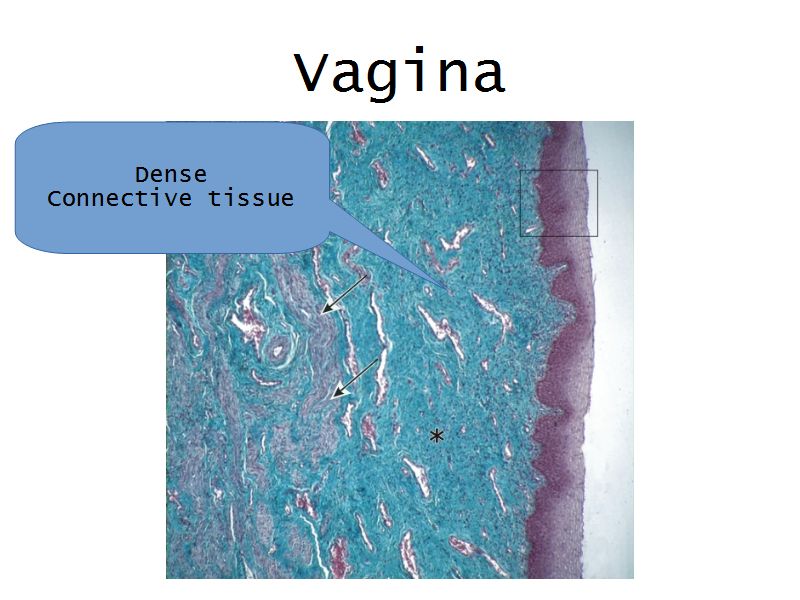

Vagina

Slide 90

Vagina

- Fibromuscular tube with 3 layers

- Inner mucosa

- Middle muscle layer

- External adventitia

Fibro = fibrous tissue

Muscular = muscle tissue

Tube = epithelium

Mucosa

- Epithelium

- Thick stratified squamous nonkeratinized

- Lamina propria

- Fibroelastic connective tissue

- Rich in elastic fibres

- Contains lymphoid elements

- Deep portion highly vascular

- No glands

Muscle layer

- Thin inner circular

- Thick outer longitudinal

- External orifice ring of skeletal muscle

Adventitia

- Fibroelastic connective tissue

- Fixes onto surrounding structure

- Blood vessels and nerves